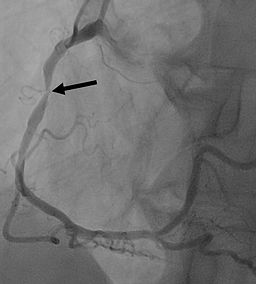

Bei hoher Wahrscheinlichkeit (> 85 Prozent) oder Nachweis einer Durchblutungsstörung in den aufgeführten Untersuchungen, sollte eine invasive Koronarangiographie (Herzkatheter) durchgeführt werden. Dabei wird ein kleiner Schlauch (Katheter) durch die Handgelenk- oder Leistenarterie zum Herzen geführt. Mit Hilfe von Kontrastmittel können dann die Herzkranzgefäße und mögliche Engstellen durch Röntgenaufnahmen sichtbar gemacht werden. Während des Eingriffs können vorliegende Engstellen mit Gefäßstützen (Stents) direkt behandelt werden.

Rechtes Herzkrangefäß mit hochgradiger Engstelle(Pfeil).